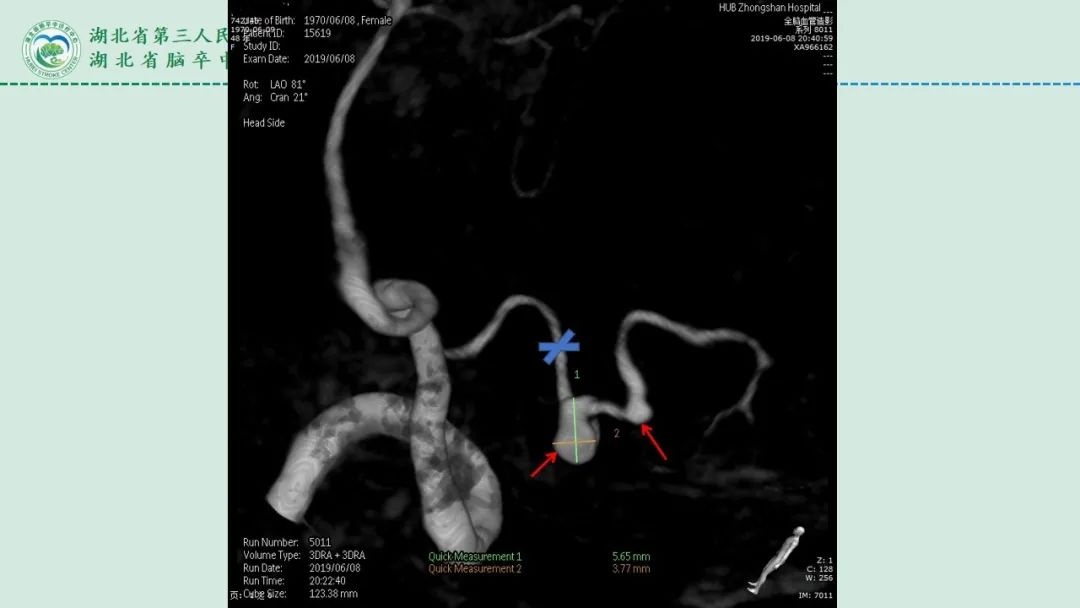

李俊教授团队:右侧PICA延髓扁桃体段多发动脉瘤

今日与大家分享的是《正海-妙术视界》第二百三十二期,由湖北省第三人民医院李俊教授团队带来的右侧PICA延髓扁桃体段多发动脉瘤,欢迎观看、分享。